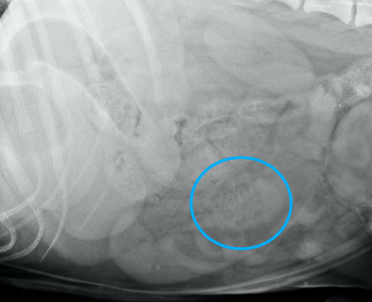

Quel est votre conclusion radiographique? Énumérez quelques diagnostics différentiels.

=> masse splénique

Ddx : néoplasme, granulome, kyste, hématome, nodule hyperplasique